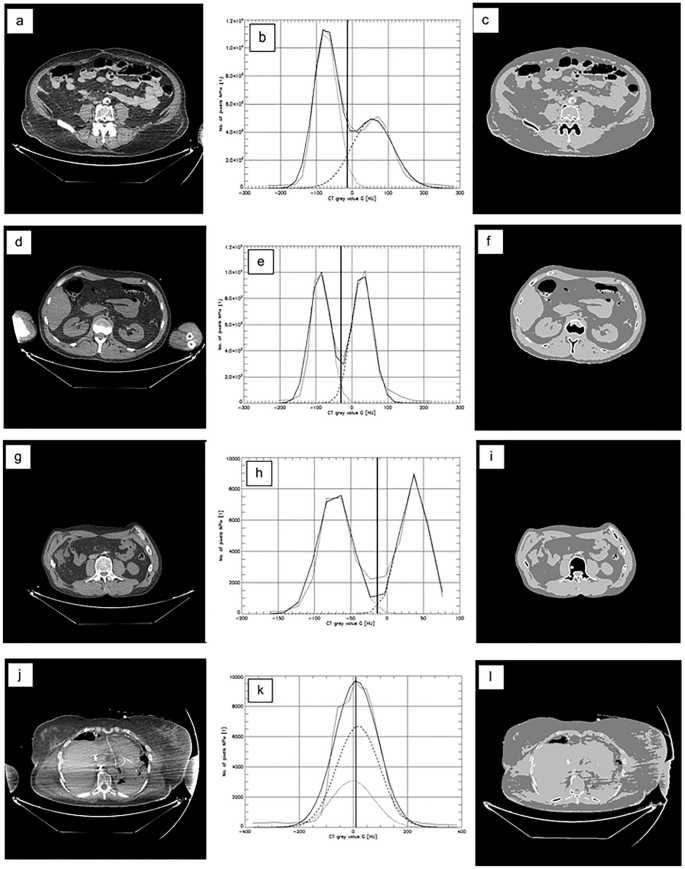

As examples of the CFES performance Fig. 5a,d,g,j show four slices Y, their grey-scale value histograms X(Y), X(Θ*), XF(Θ*), XM(Θ*) (Fig. 5b,e,h,k) and the respective quasi-segmentation results W*(Y) (Fig. 5c,f,i,l). Horizontal image-line 1, 2, 3, 4 corresponds to LFD 06, 22, 24, 16 (see Table 1) respectively. While the first three slices (a), (d), (g) lead to acceptable results, slice (j) was added as a poor result caused by weak contrast and artefacts. LFD 16 was excluded from our statistical evaluations.

Four slices Y in (a), (d), (g), (j) from four different persons at different abdominal positions. Respective histograms with thin line = measured data X, thick line = fitted histogram X(Θ*) , partial histograms XF(Θ*), XM(Θ*) in (b), (e), (h), (k) and quasi-segmentation results W*(Y) in (c), (f), (i), (l). The parameter α was α = 1.